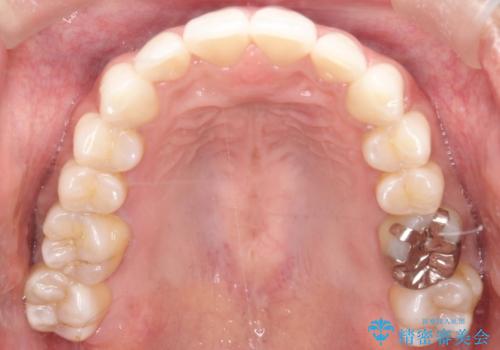

精密検査の結果、歯を並べるためのスペースが不足していましたが、抜歯をせずに改善したいというご希望があったため、IPR(歯の側面をわずかに削る処置)と、奥歯を後ろに動かす「遠心移動」を組み合わせる計画を立案。透明なマウスピース装置であるインビザラインを使用し、無理のない範囲でスペースを確保しながら歯列を整えることとしました。

治療では、マウスピースの設計に基づき、奥歯から順に後ろへ移動させる遠心移動を行い、前歯のためのスペースを作りました。同時に、数箇所の歯の間にIPRを施すことで、歯の健康に影響のない範囲で精密に隙間を確保しました。

1年半の治療期間を経て、重なり合っていた前歯はスムーズに整列し、理想的なアーチ状の歯並びへと改善されました。抜歯を行わずに治療を完了したことで、噛み合わせのバランスを維持しながら、審美性を大きく向上させることができました。現在は保定期間に入り、美しい状態を維持されています。